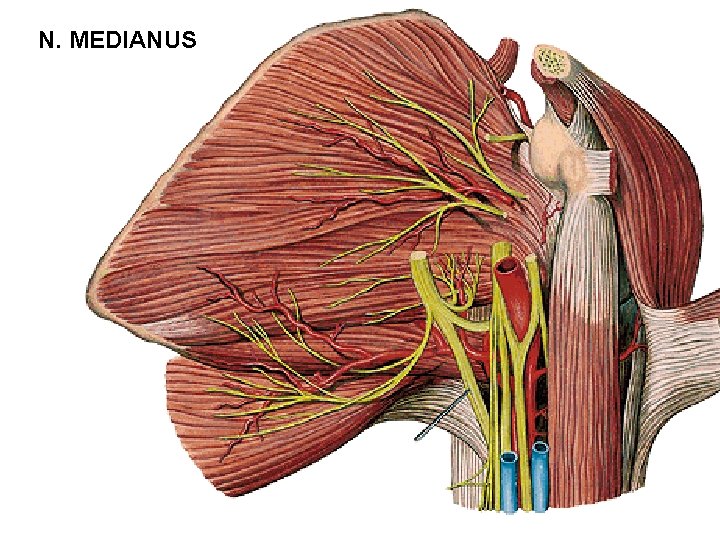

N. MEDIANUS

N. MEDIANUS (Sulcus bicipitalis medialis)

N. MEDIANUS

N. MEDIANUS

N. MEDIANUS - rr. articulares - rr. musculares - m. pronator teres - m. flexor carpi radialis - m. palmaris longus - m. flexor digitorum spf. - n. interosseus antebrachii ant. - m. flexor pollicis longus - radial half of m. flexor dig. prof. - m. pronator quadratus - r. palmaris

N. MEDIANUS - r. thenaris - m. abductor pollicis brevis - m. flexor pollicis brevis – caput superficiale - m. opponens pollicis - nn. digitales palmares communes - mm. lumbricales (I, II) - nn. digitales palmares proprii - r. communicans cum nervo ulnari